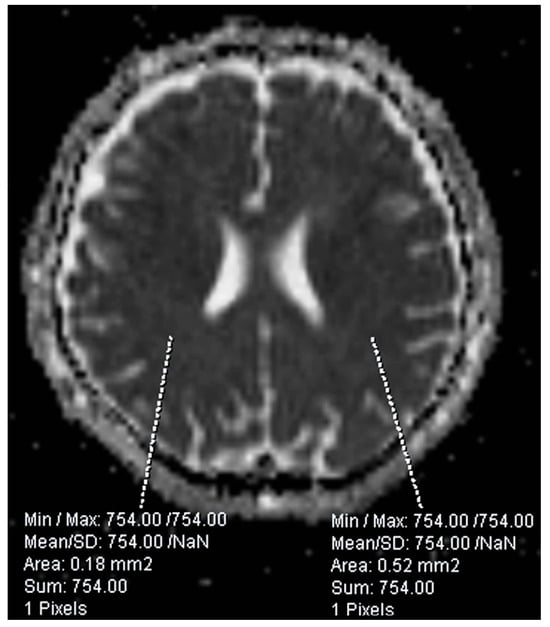

For each ROI, quantitative parameters—including surface area and the minimum, maximum, mean, and standard deviation of ADC values—were extracted. All measurements were performed using SyngoVia Plaza software XA51 (Siemens Healthineers, Erlangen, Germany) (Figure 1).

Figure 1. Example of ROI placement in cerebral white matter. Small, circular ROIs were symmetrically positioned within homologous regions of both hemispheres.

Diffusion-weighted images and their corresponding apparent diffusion coefficient maps were transferred to a dedicated imaging workstation for quantitative analysis. ADC measurements were obtained from manually placed circular ROIs located within the white matter of the middle cerebral artery territory, avoiding gray matter and cerebrospinal fluid to minimize partial volume effects. ROIs were placed symmetrically in homologous locations across both hemispheres to improve measurement consistency. All ROI placements and measurements were performed by a single experienced rater, using the same anatomical landmarks in each subject to ensure reproducibility. Preprocessing was limited to co-registering b = 0 images (T2-weighted equivalent) to the ADC maps to improve localization accuracy [22]. No additional spatial smoothing or motion correction was applied, as image quality control excluded cases with significant artifacts.